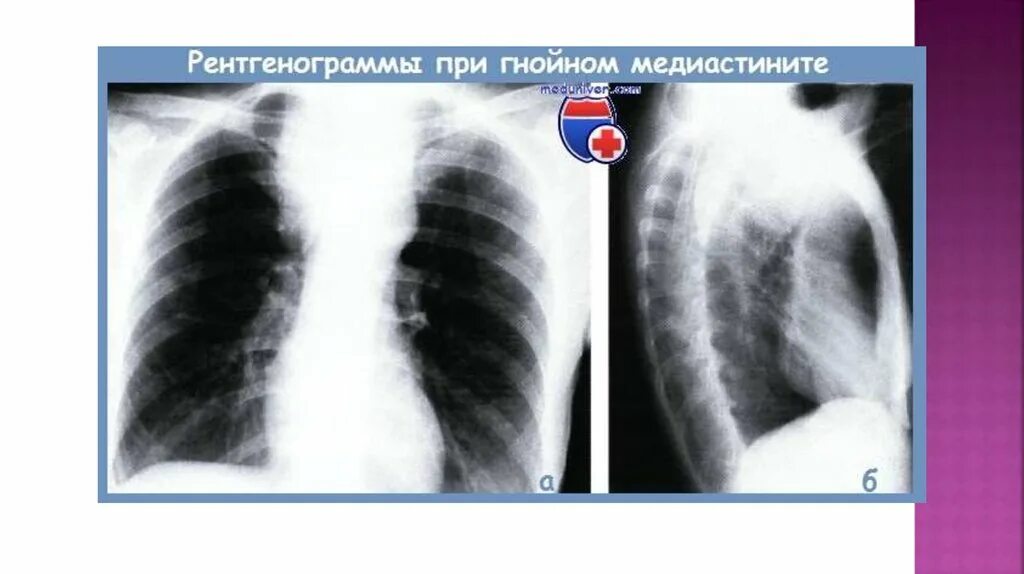

Медиастинит причины